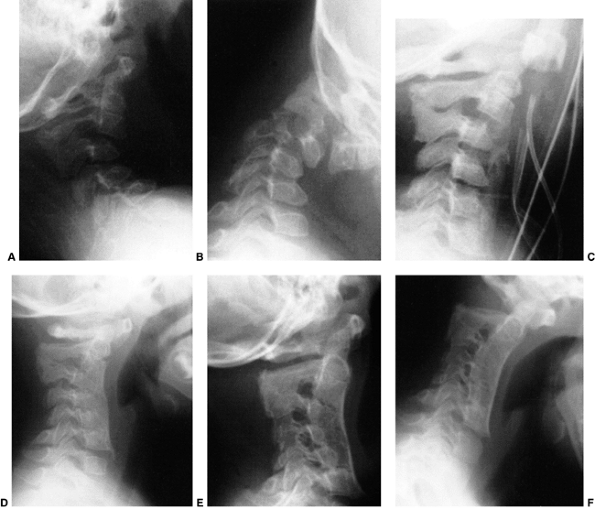

![]() |

Figure 22.8

This girl, 3 years and 9 months of age, had a history of vertex headaches for 1 year. One month prior to presentation, she developed a painful, left-sided torticollis. A: Plain lateral radiograph shows fusion of C2 and C3 and absence of the ring of C1 with occipitalization. B: Magnetic resonance image (MRI) shows an Arnold-Chiari malformation, with herniation of the cerebellar tonsils into the foramen magnum (arrow). Also note the cordal edema (arrowhead). C: The child underwent an occipital decompression and laminectomy to C3, posterior cervical fusion from the occiput to C4, and halo cast immobilization for 4 months. Flexion and extension lateral radiographs 1 year after treatment show solid incorporation of the fusion from C2 to C4, with dissolution of the graft from the occiput to C2. However, there is no atlantooccipital instability. The child’s symptoms resolved. |